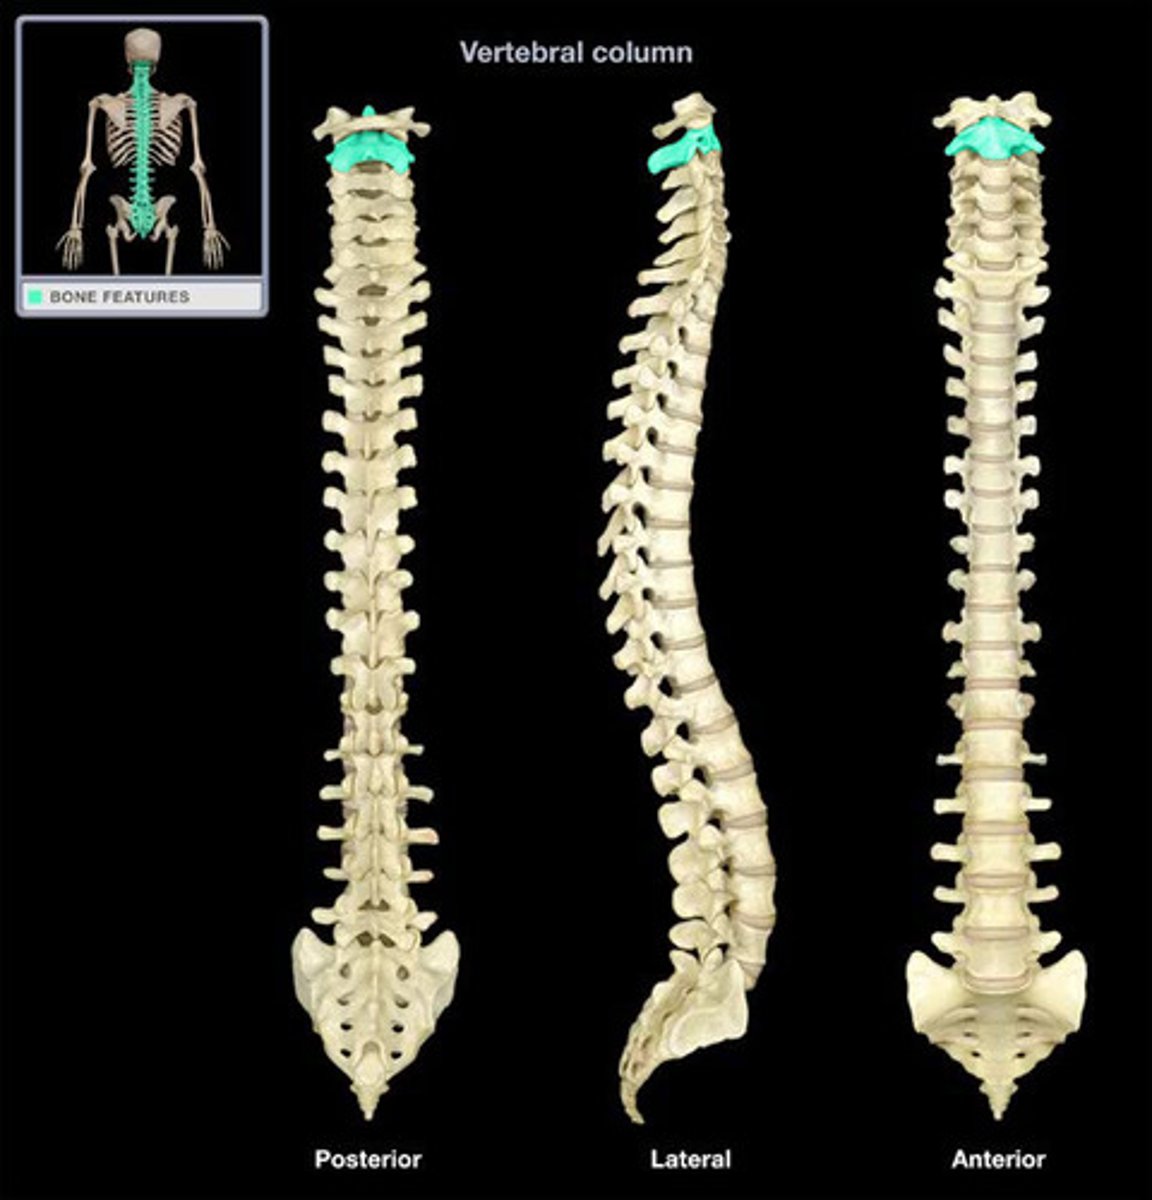

Cervical Vertebrae 7

Thoracic Vertebrae 12

Lumbar Vertebrae 5

Sacrum 5 fused

Coccyx 3-5